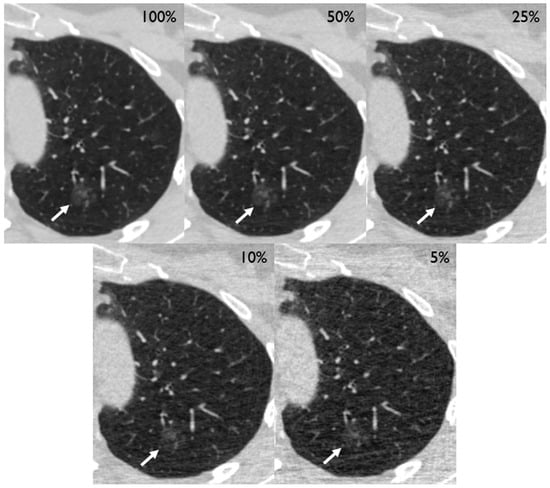

After preparation of the simulations, the CT scans of 210 patients (mean age [SD] 64.5 [9.2] years, 87 females [41%]) containing 250 tumors of the lung (201 solid, 28 part-solid, and 21 ground glass) could be included in the analysis (Table 1). Two exemplary cases are depicted in Figure 2 and Figure 3. Eight patients had to be excluded due to technical reasons, such as incomplete coverage of the lungs.

Figure 3.

Different dose level simulations depicting a 14 mm ground-glass nodule in the left upper lobe of a 75-year old female (white arrow) with left-sided chest pain. The lesion turned out to be a primary pulmonary adenocarcinoma.